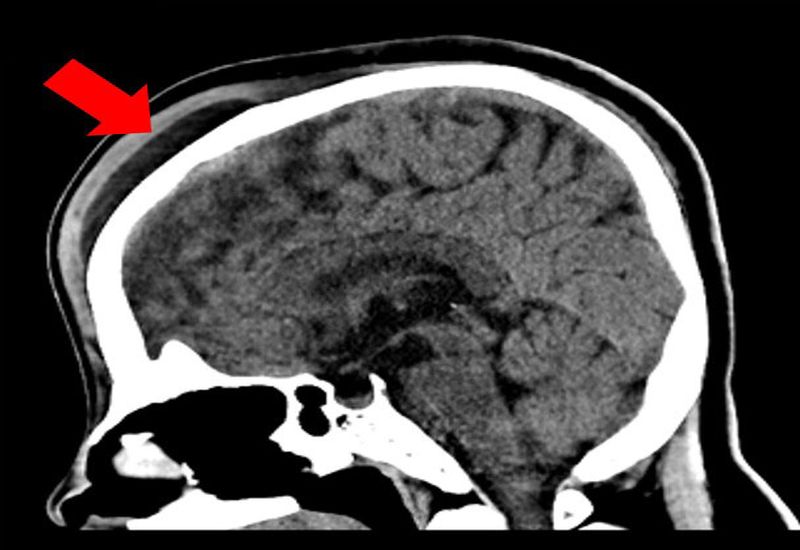

치료 사례인 37세 여성환자는 외상 후 두피하혈종이 발생해 참조은병원을 찾았고, CT 검사에서 전두골 골절을 확인, 압박드레싱과 바늘흡인 치료에도 재발하는 난치성 경과를 보였다.

의료진은 CT 혈관 촬영으로 양측 표재성 측두동맥(STA)과 후두동맥(OA)에서 공급되는 비대 혈관들이 혈종 주위 망상 혈관 네트워크가 형성됨을 확인했다.